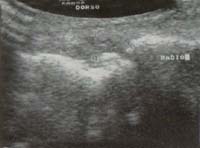

SR, Masculino 56 años, a quien hace 20 años se le diagnosticó “Lupus seronegativo” por glomerulonefritis membranosa. Durante 20 años el paciente recibió tratamiento a base de esteroides e inmunosupresores, lo que lo hizo corticodependiente. Desde hace 5 años el paciente viene presentando un cuadro de poliartritis, especialmente de metatarsofalángica, tobillos, rodillas, codos, con períodos intercríticos de 2 a 4 semanas y notó la presencia de múltiples tofos en rodillas, codos, especialmente en la muñeca izquierda, donde se demostró un tofo subdérmico por estudio ecográfico y gamagráfico (Figura 7 A y B), e hiperuricemia con hiperuricosuria. En la radiografía de muñecas y de rodillas se evidenció la presencia de calcificación que correspondieron por estudios de líquido sinovial a cristales de urato monosódico y pirofosfato cálcico.

Figura 7 A. Gamagrafía de muñecas donde se observa hipercaptación en muñeca izquierda, sitio de localización de tofo subdérmico.

Figura 7 B. Ecografía de muñeca donde se observa la presencia de tofo calcificado rodeado por líquido (Ver asteriscos).